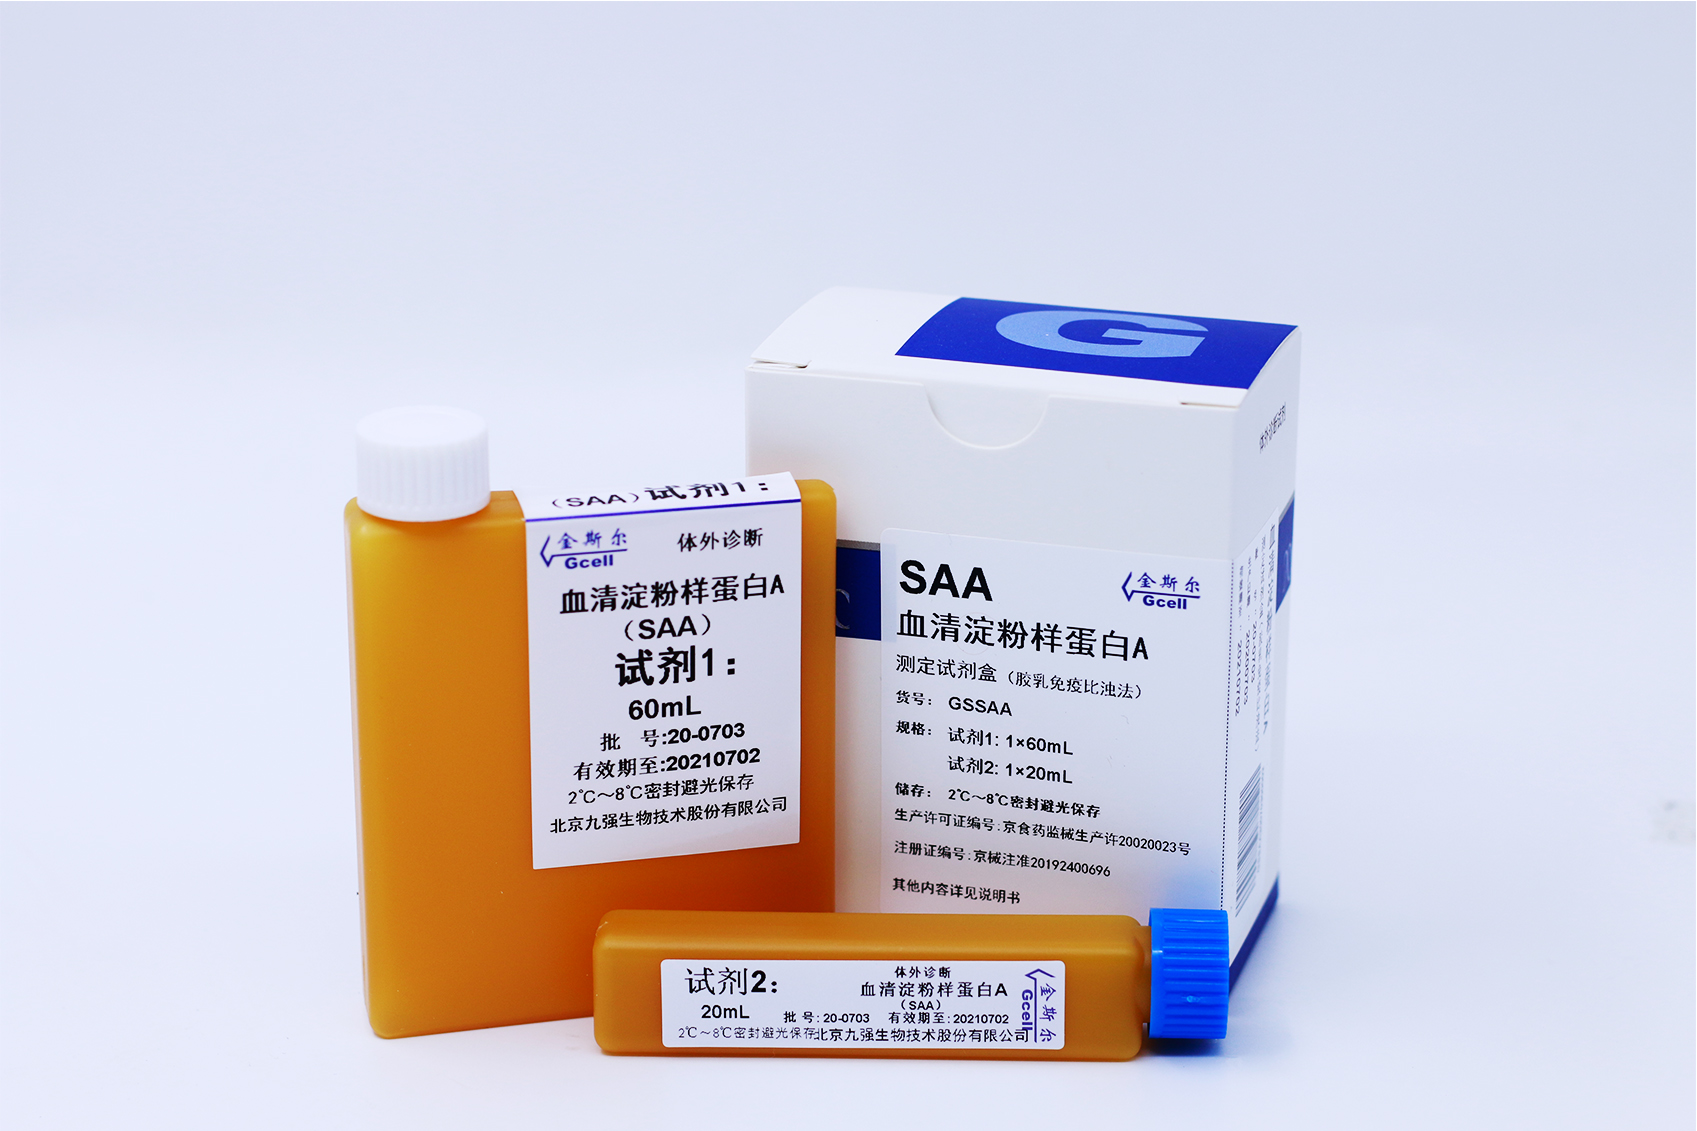

特种蛋白类

Special Protein Panel